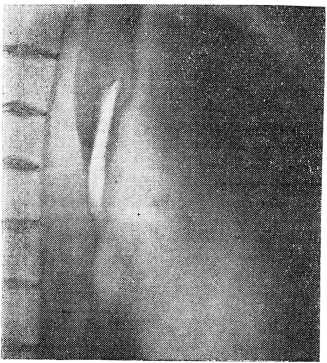

3/V-60 г. мы произвели больному томографическое исследование. Послойные снимки уточнили место расположения отломка ножа в левом главном бронхе (рис. 2).

Рис. 2. Сагиттальная томограмма, выполненная отступя от срединной линии на 1,5 см левее. Отломок ножа в левом главном бронхе. Конец его выступает над бифуркацией.

Бронхоскопия от 7/V-60 г. (проф. Н. Н. Ло- занов) это подтвердила и установила, что конец ножа несколько выступает в просвет трахеи.